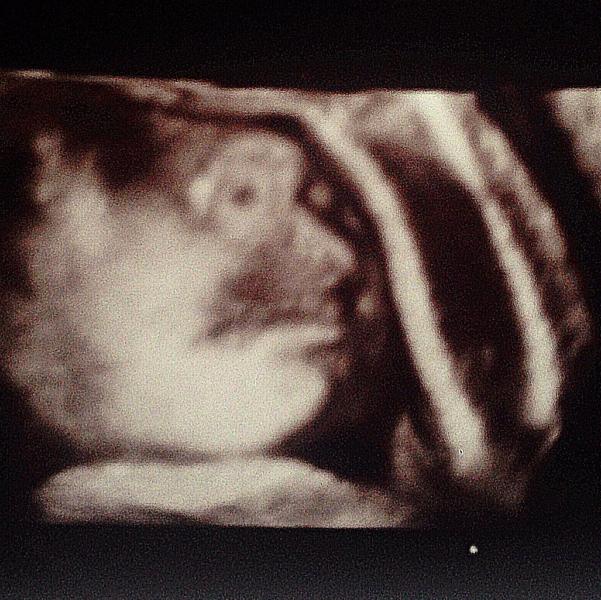

Были сегодня на 3-ем скрининге. Все отлично!☺️ реснички у сыночка уже 5 мм., волосиков на головке уже много☺️ и ВЕС: 2,126 кг. (опережает на 2 недели)... Ставят "Тенденция к крупному плоду". Я немного шокирована, так как вроде особо не в кого быть крупным☺️ ну теперь то понятно почему я каждый день по 200 гр плюсом😝 главное, что все хорошо! Подмигивал нам на узи и причмокивал-такая прелесть☺️☺️☺️ теперь боюсь, чтобы к родам не был крупным (сказали может еще нормализуется вес)... Не хотелось бы сложнос...